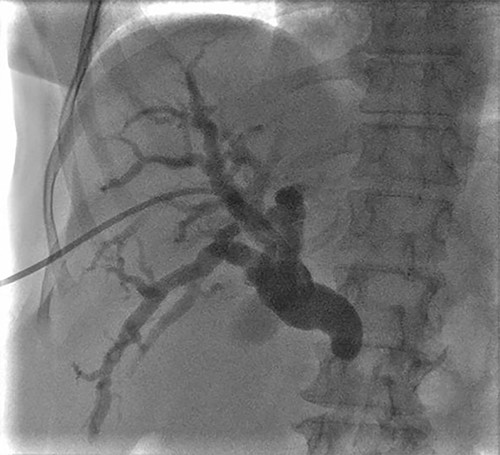

PTC showing dilation of intrahepatic biliary tree with abnormal tapering in the mid bile duct and lack of contrast filling distally.